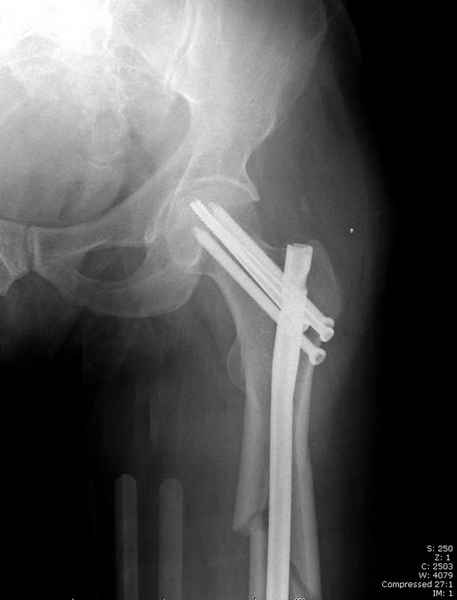

Учитывая, что случай ургентный, больной поступил вечером, не стали делать вытяжение и срочно провели операцию по фиксации перелома бедра антеградным штифтом Versa Nail от DePuy.

Для профилактики дальнейшего раскола в шейке предварительно во время проксимального рассверливания спереди и сзади провели временные спицы, которые в дальнейшем были заменены на шурупы (miss nail method)